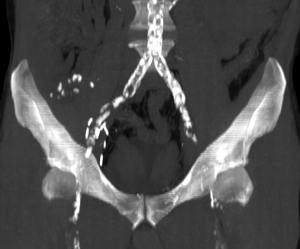

The CT scan is expected to provide information about the location and length of the plaques, their circumferential character or lack thereof, their degree of stenosis, and their thickness and density (3). When a CT scan without contrast is performed, only the calcified plaques are visible, allowing the radiologist to describe their location, length, and, if applicable, their circumferential character. The scan without contrast has an advantage over the scan performed after injection in enabling a better analysis of the thin vascular calcifications. Thanks to 3D volume rendering technique (VRT) reconstruction and maximum intensity projection (MIP) imaging, the CT scan at the arterial phase after intravenous injection of contrast medium makes it possible to analyze the atheroma plaques in greater detail, and to make global representations of the aorta and its branches. In the absence of intravenous iodinated contrast injection however, MIP only shows a global view of the arterial calcifications (Figure 1).